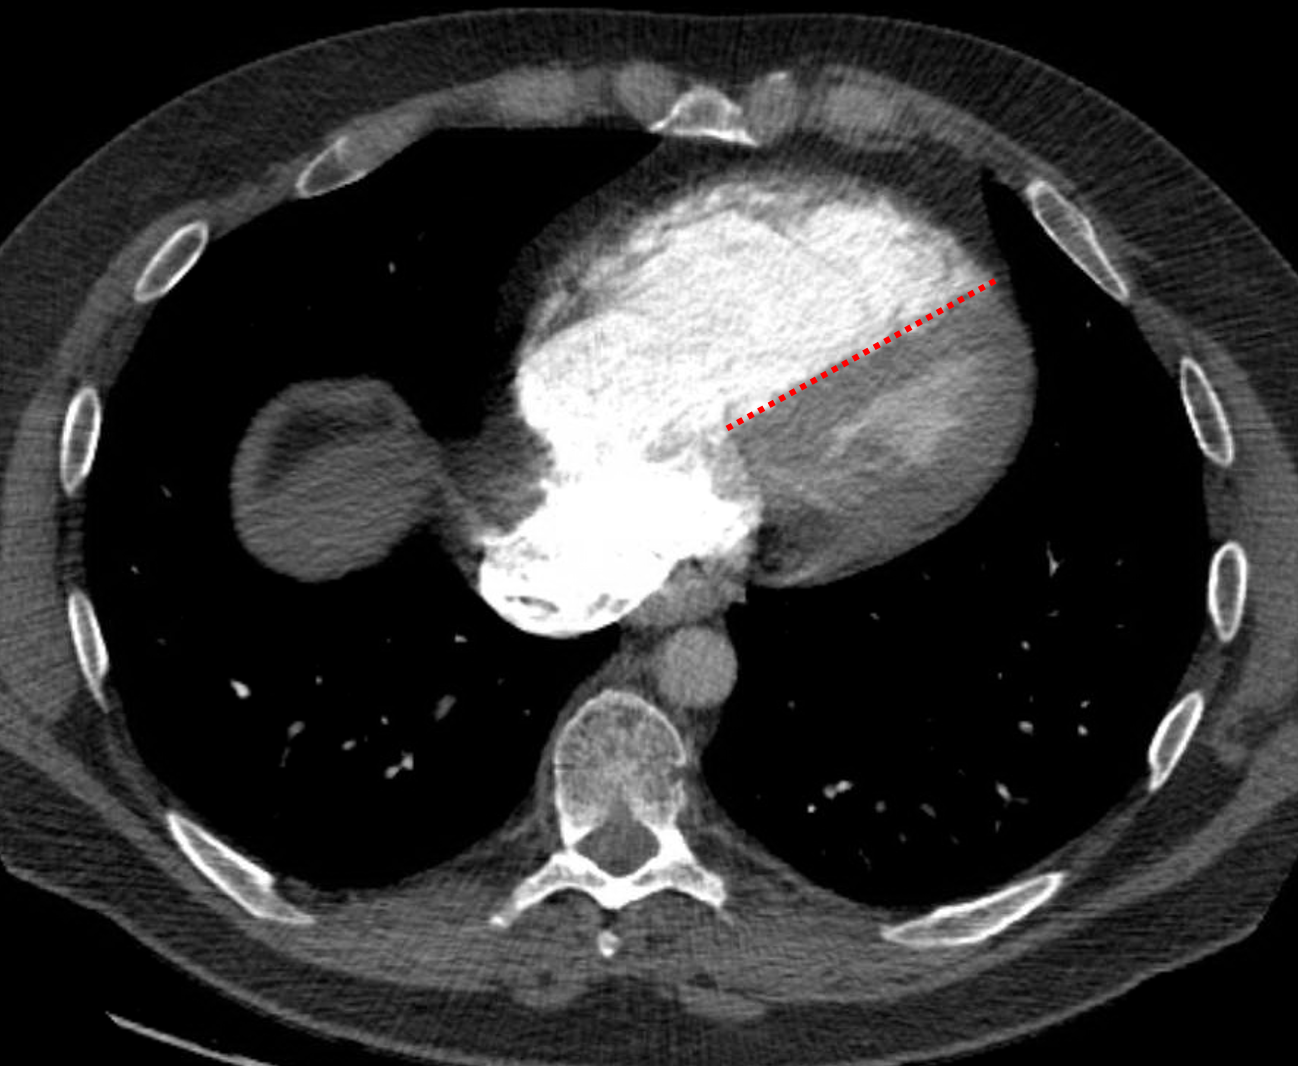

Age: 42

Sex: Male

Indication: Chest pain, dyspnea

Sample ReportLarge burden of acute pulmonary embolism with findings concerning for right heart strain.